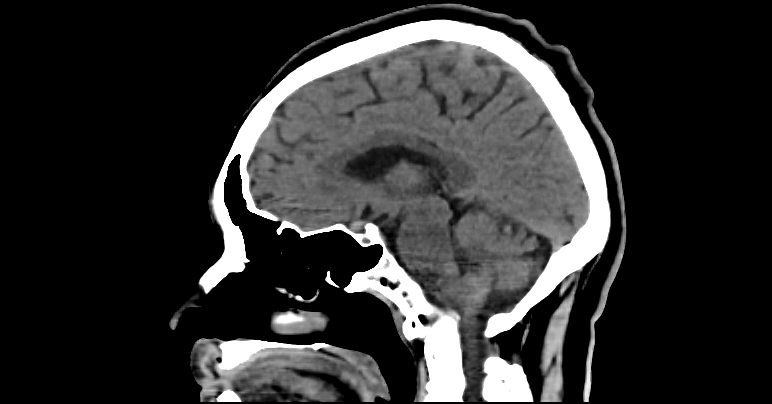

Caso clínico: Invaginación basilar diagnosticada en tomografía sagital

Tomografía computarizada simple con reconstrucción multiplanar, enfatizando plano sagital de la unión craneocervical.

En reconstrucción sagital se observa ascenso del proceso odontoides por encima de la línea de Chamberlain, protruyendo hacia el foramen magno. El odontoides se encuentra impactando la cara ventral del bulbo raquídeo, con reducción del espacio óseo del foramen magno.

Se evidencia disminución del ángulo clivus-canal y alteración en la alineación de la unión craneocervical. No se identifican fracturas agudas ni lesiones líticas o blásticas asociadas.

Hallazgos compatibles con invaginación basilar.